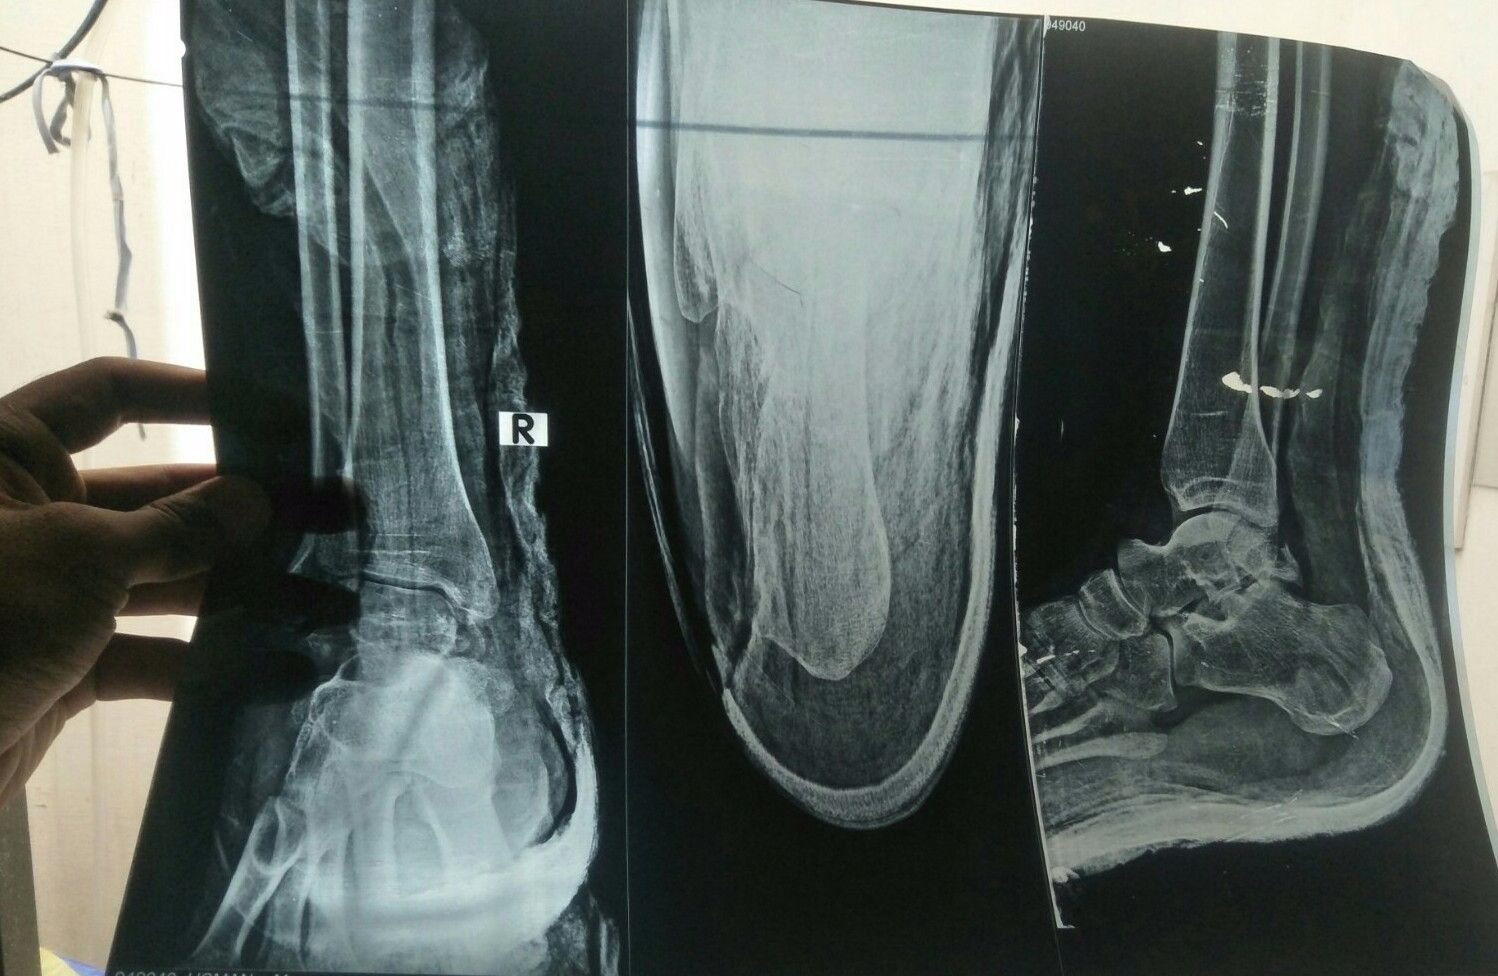

Koi dctr senior dctr guide kry ye xray h.. Ye oprate bgair ni jur skhti plaster ky Sth ?? Plz anser or kb tuk oprate ky bd chl skhey ga kitni rest h Ya oprate he ho ga to kesy ho ga cut lgye ga kia daly gye ?? Or hadi jor kah rhy h jur jaey gi oprate ky bgair b.. Plz guide

need clear xray

More X-rays views required. These X-rays are not good and not helpful

Can be managed in cast. No surgery required

cannot comment without physical examination. This patient requires 3D CT reconstruction images before any decision to made.

Show Ap view also to be confirmed cast n not weight bearing can also heal

need to examine the pt and ap view also required for further management

Plz post AP view of this x ray as well.... Then it can be commented

Hi, you need to get MRI to decide about treatment. Thanks